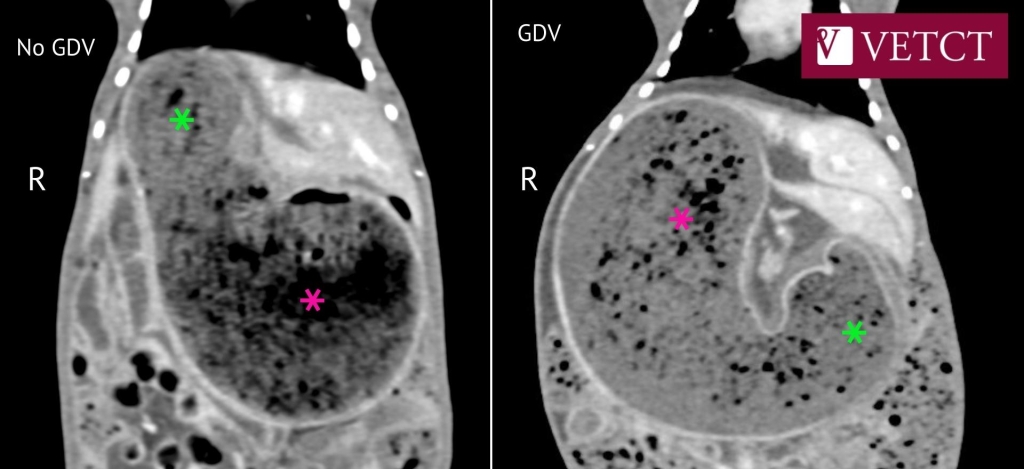

VetCT report of a CT scan showing GDV in a rabbit - The pylorus (lime green stars) denoted by the thick pyloric wall is located on the left side of the abdomen and the fundus (dark pink stars) is right laterally located.

Gastric dilation is a common condition in rabbits, however incidence of GDV is poorly documented. Dr Dean Felkler, Founder and CEO of Exotic Vet Support and senior clinician at Tai Wai Small Animal and Exotic Hospital, highlighted the importance of accurate and early diagnosis in a recent case of a 7yr old rabbit that was presented for anorexia and hadn’t passed faeces for over 12hrs. Dr Dean says, “A full diagnostic investigation was performed. From the radiographs it is difficult to appreciate the GDV. However, on the CT scan, reported by VetCT, it was very obvious when compared to the normal stomach orientation.”